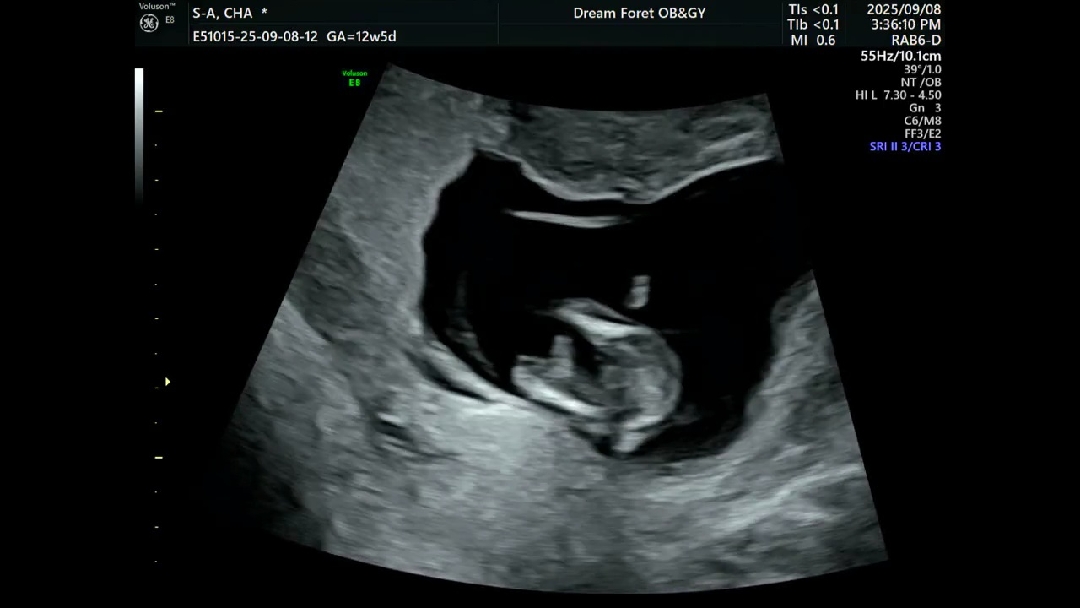

아들딸 상관없다면서도 은근히 딸얘기많이하는 남편때문에 한번 여쭤봐요 ~ 다리사이인데 뭐가 보이는게 있을까요 ??

아들인거 같아요